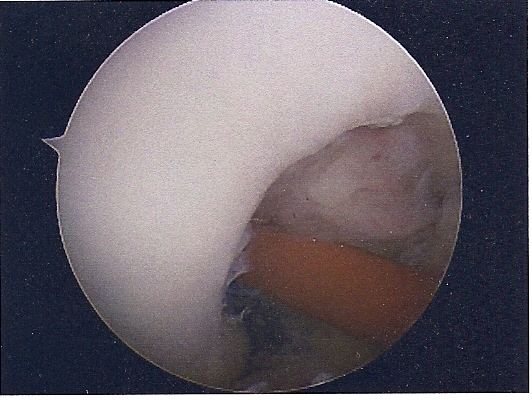

She had ACL replacement surgery on March 28th, using Bone-Patellar-Bone graft from her own patellar tendon. These are the images are scanned from pictures taken by the scope during the surgery. We were supposed to get a DVD of the procedure, but forgot to remind him on the day of the surgery. Oh well...

ACL

NOTCH